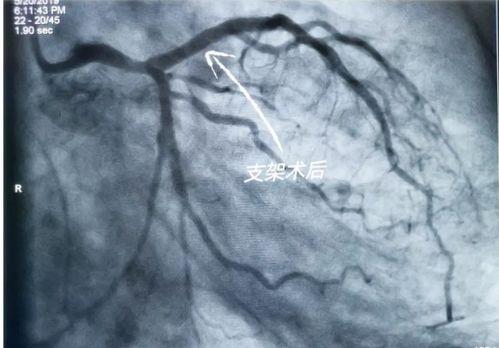

国产心脏支架在我国的应用非常广泛。据统计,我国每年约有数十万例心脏支架手术,其中大部分采用了国产心脏支架。这些支架在临床应用中表现出良好的效果,为患者带来了福音。